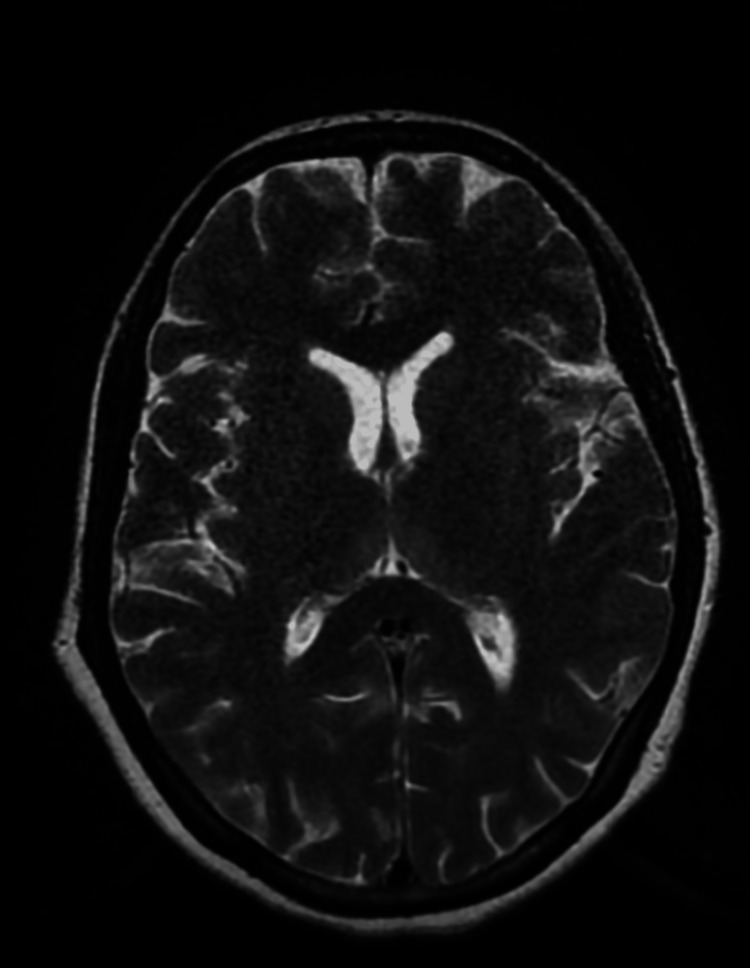

Other investigations were normal. She was diagnosed with hyperemesis gravidarum and was managed conservatively. Infusion of potassium chloride (KCL) injection 40 mEq in 500 mL Ringer’s lactate drip was intravenously given for hypokalemia. On the third day of the injection of metoclopramide hydrochloride, the patient had an acute convulsive episode with vertical and horizontal nystagmus with debilitating ataxia. Levetiracetam 1 g injection was intravenously given stat. And on an emergency basis, the physician’s opinion was taken. As per the advice of the physician, a brain plain magnetic resonance imaging (MRI) was done, which revealed no significant abnormality (Figure 1). Neurologist opinion was taken in view of this event. Refraction testing, fundus examination, and antinuclear antibody (ANA) test using the immunofluorescence assay (IFA) method were advised by a neurologist. ANA test by IFA suggested a negative result. A complete ophthalmic examination by an ophthalmologist revealed upbeat nystagmus, as shown in Video 1. As per the physician’s advice, the injection of metoclopramide hydrochloride was withheld in suspicion of EPS of the drug. The patient was continued on injection of ondansetron, and the injection of thiamine was started via the intravenous route. The patient’s symptoms reduced significantly after stopping the injection of metoclopramide hydrochloride, and nystagmus also disappeared. The patient was clinically asymptomatic and was discharged on doxylamine 10 mg tablet thrice daily.

Figure 1. Axial T2WI of plain brain magnetic resonance imaging suggestive of no obvious abnormalities.

T2WI, T2-weighted image